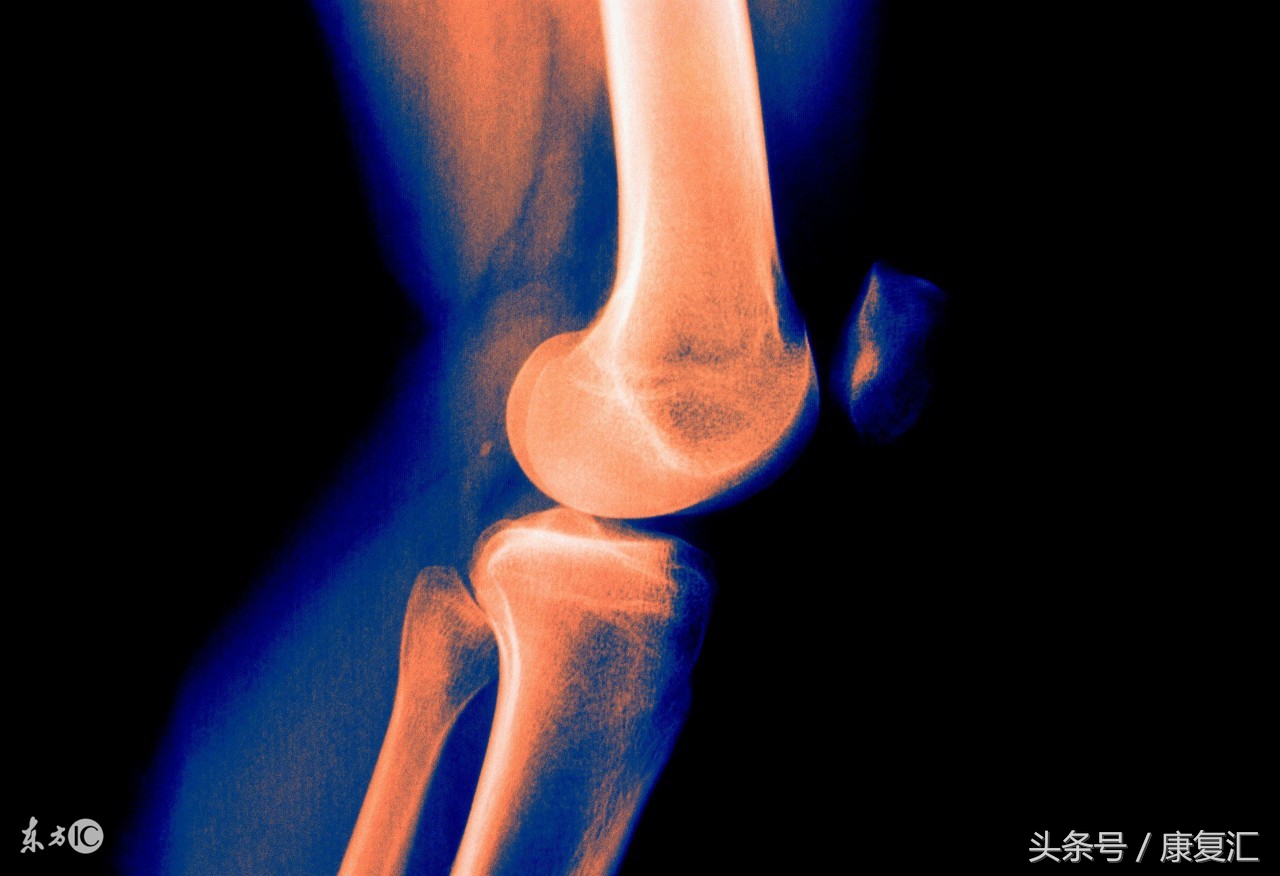

OA 是一种慢性进行性关节疾病,以软骨变性和丢失,以及关节边缘和软骨下骨质再生为特征,多以间断性的慢性关节疼痛、僵硬、肿大,及伴关节功能障碍为主要表现,严重者关节畸形甚至瘫痪。